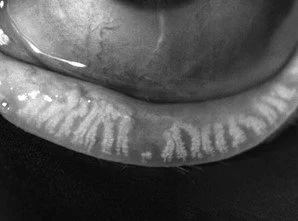

Meibomian Glands pre IPL procedure

Meibomian Glands following IPL treatment